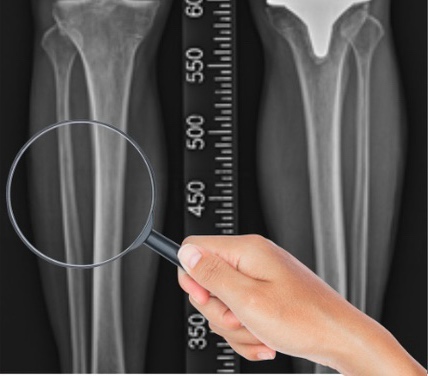

사진에서 보는 것과 같이 왼쪽, 기존 장비는

발판도 높고 손잡이도 부실해 보이는데

오른쪽 새로운 장비는 발판과 손잡이도 안정적으로 보이네요

그리고 무었보다 결과물이 이렇게

차이가 난답니다!

뭐가 다른거지??

자세히 살펴보면

혹시 골절아니야?? 싶을 정도로

어긋난 부분이 보이실거에요

기존 장비는 다리 전체 사진을 찍을때 세번으로 나눠서 찍은 다음 사진을 합치는 방식이었다고 해요.

그래서 사진을 합치는 과정에서

어긋나 보이는 부분이 생길수 있는거죠!

하지만 새로운 스캐노그램 장비는 한번에 다리 전체를 촬영할 수 있기때문에

사진을 보시면 어긋난 부분없이 메끄럽죠?

오다리는 각도를 재야하기때문에

겹치는 부분없이 메끄러워 좀 더 정확하게 체크 할 수 있습니다